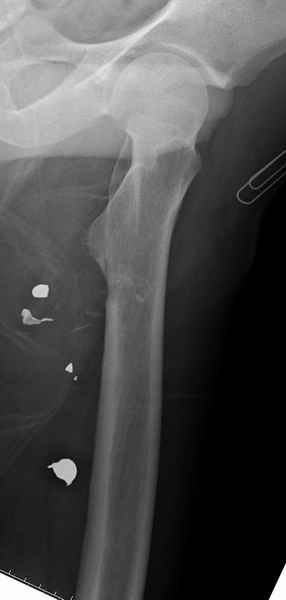

Больной с огнестрельным переломом бедра с вовлечением около 15% медиального кортекса, входное отверстие около 1 см в диаметре; стабильный, без сосудистых и неврологических признаков.

Что делать: гипс, костыли, операция?

Литературные данные о влиянии кортикального дефекта на стрессовые переломы в длинных трубчатых костях в основном встречаются в онкологии, например кортикальный дефект более 50% имеет больше шанса стрессовых переломов, чем в нашем случае.